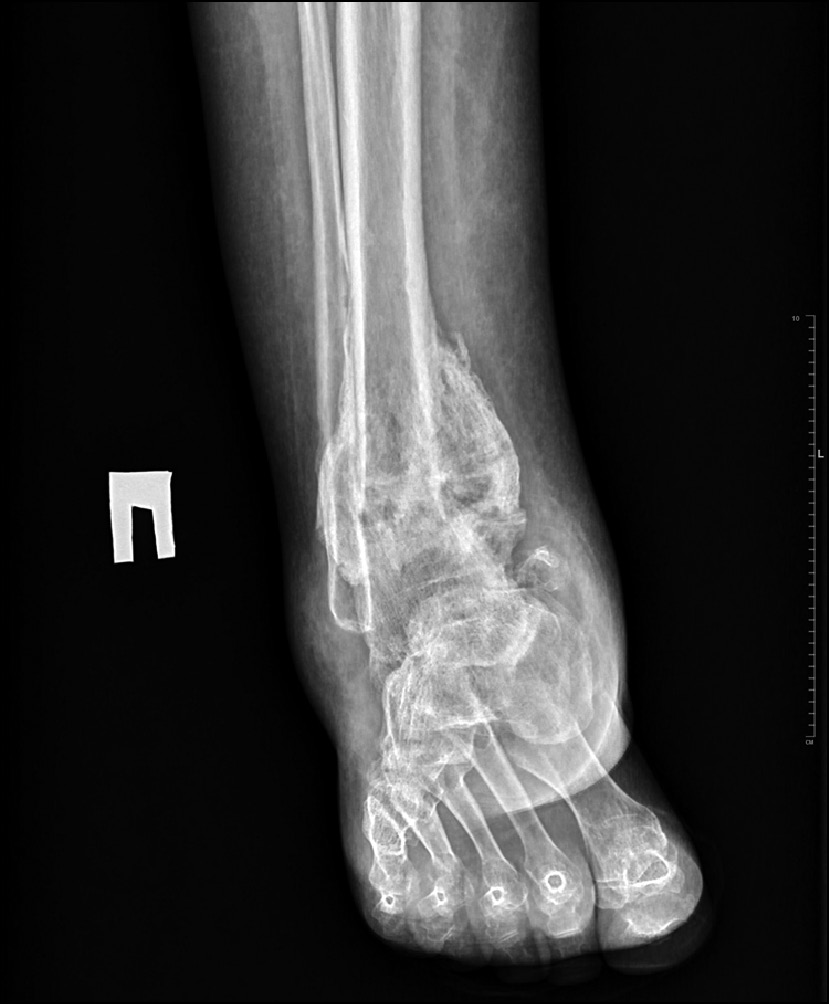

Рис. 5. Рентгенограммы через 8 месяцев после операции.

Fig. 5. X-ray image 8 months after surgery.

Разрешена постепенно возрастающая нагрузка в полимерной иммобилизирующей повязке в течение 4 месяцев после демонтажа аппарата Илизарова, по истечении которых рентгенологически определялись увеличение МПКТ до предоперационных значений, ремоделирование костной ткани — перестройка общей трабекулярной текстуры. Был разрешён переход на ортопедическую обувь с компенсацией укорочения конечности (4 см). К этому времени болевой синдром пациентку не беспокоил, патологическая подвижность отсутствовала, однако сохранялся слабо выраженный отёк дистального сегмента конечности (+1,5 см) (рис. 4, 5). В течение данного периоперационного периода лечения осложнений не отмечалось.